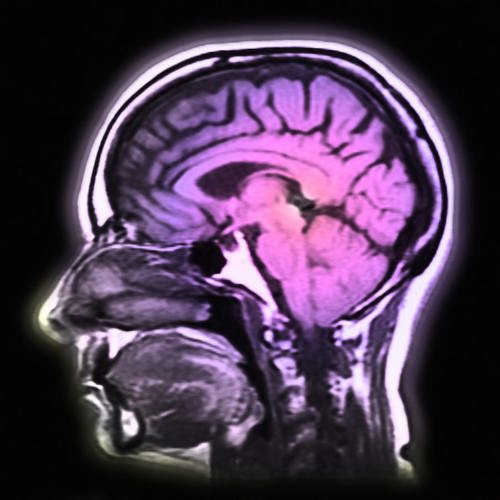

Dyslexia and Brain Wiring

Before you're even born, your body is hard at work building your brain. Part of this building involves making sure your nerve cells are put in the right place. And part of the building is making sure your nerve cells can talk to each other. They do this by reaching out to touch each other with lots of branches, like a tiny little tree.

This communication between cells is very important. It's what lets your brain control the things it does. Things like walking, talking, solving math problems, and reading.

Two of the genes that scientists think are involved in dyslexia are called DCDC2 and DYX1C1. They both help your nerve cells move to the right place while your brain is being built.

Another gene that scientists think is involved in dyslexia is called ROBO1. This gene helps your nerve cells to know where to send out their branches to talk to other nerve cells.